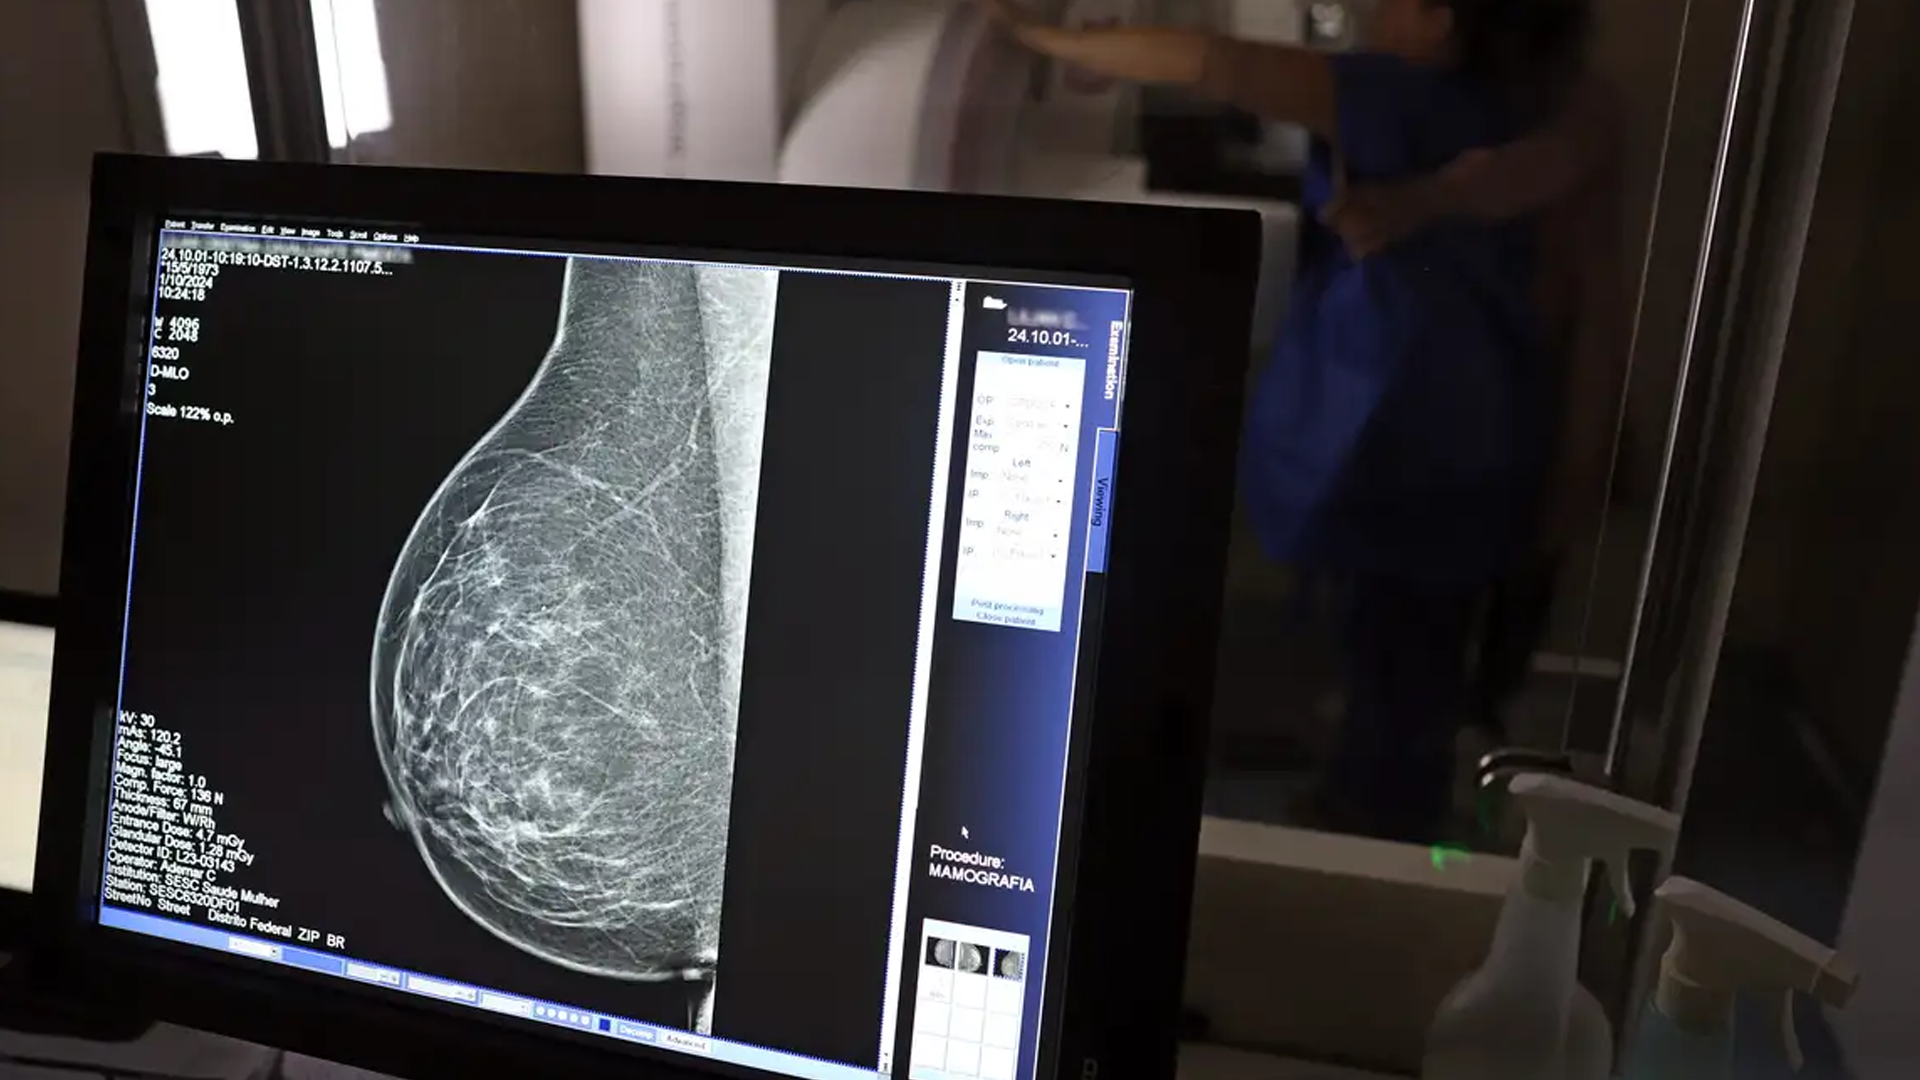

Ministério da Saúde passa a recomendar mamografia a partir dos 40 anos

O Ministério da Saúde passou a recomendar o acesso a mamografia, via Sistema Único de Saúde (SUS), para mulheres de 40 a 49 anos – mesmo que não haja sinais ou sintomas de câncer de mama. De acordo com a pasta, a faixa etária concentra 23% dos casos da doença, e a detecção precoce aumenta as chances de cura.

Até então, a orientação era que o exame fosse feito a partir dos 50 anos.